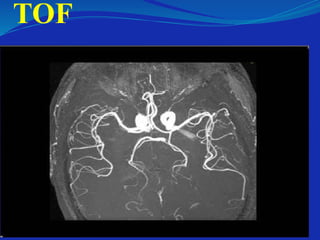

Magnetic Resonance Angiography

 May be done after injecting contrast (Gadolinium) or

without(TOF)

 Flowing blood changes the way that radio waves

interact with the water in blood

– May give more signal (IN TOF)

– May give less signal (AS FLOW VOID)

TOF